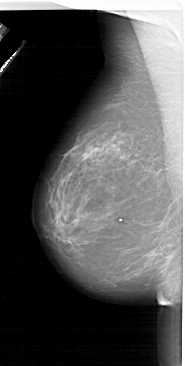

A_1620_1.LEFT_CC

LEFT_CC LINES 5911 PIXELS_PER_LINE 3181 BITS_PER_PIXEL 12 RESOLUTION 43.5 NON_OVERLAY